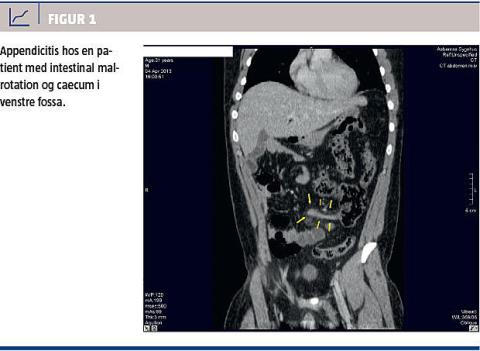

Der blev rejst mistanke om appendicitis acuta, men pga. de atypiske klinisk fund og anamnesen blev der foretaget akut CT af abdomen med intravenøs kontrast. Intraabdominalt fandt man en fortykket appendix og reaktion i det omkringliggende fedtvæv. Caecum var beliggende i venstre side, og appendix strakte sig derfra til lidt over midtlinjen i højre side (Figur 1). Samtlige colonafsnit var beliggende til venstre for midtlinjen. De øvrige intraabdominale organer var upåfaldende. Der blev herefter foretaget laparoskopi med Verres kanyle under venstre kurvatur pga. malrotationen samt port i højre side af abdomen og over symfysen, og der blev foretaget en ukompliceret laparoskopisk appendektomi med fjernelse af en inflammeret appendix. Efterforløbet var ukompliceret.